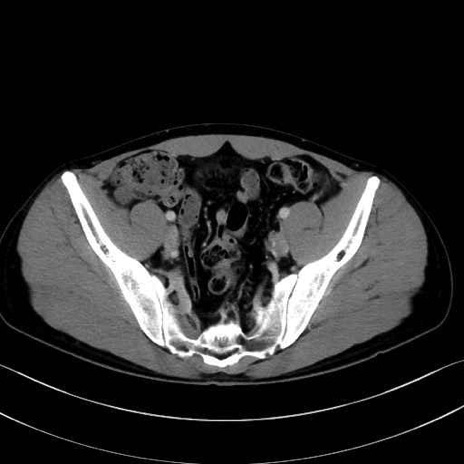

大腿筋膜張筋 (Tensor fasciae latae)